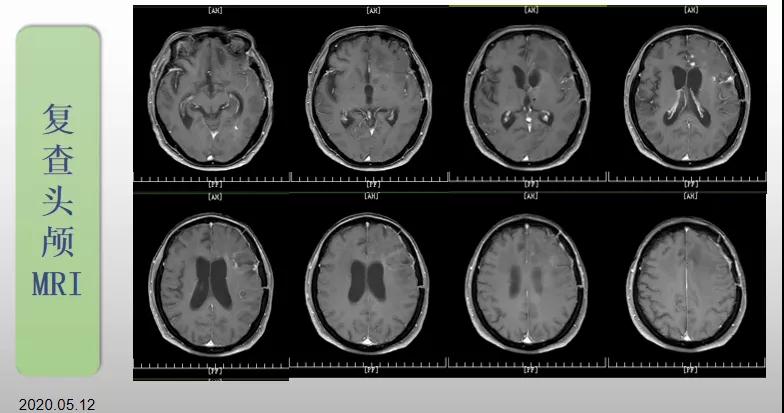

綜合治療 電場治療助70歲患者回歸正常生活

70歲的郝女士去年曾在外院查出“左額島葉”膠質(zhì)母細(xì)胞瘤(WHO Ⅳ級),并做了左側(cè)額島葉占位性病變切除術(shù)。術(shù)后進(jìn)行了同步放化療。由于治療條件有限,郝女士慕名來到我院就診。賀世明主任率領(lǐng)醫(yī)護(hù)團(tuán)隊(duì)立即為郝女士進(jìn)行了全面的檢查,決定為其進(jìn)行綜合治療 電場治療。經(jīng)過三個(gè)多月的綜合治療,患者復(fù)查頭顱MRI病變較前明顯縮小。出院時(shí),郝女士神志清醒,睡眠飲食正常,說話很流利?!拔沂翘芍M(jìn)來的,現(xiàn)在不用人攙扶,自己就可以走出病房了?!焙屡坷t(yī)護(hù)人員的手說。